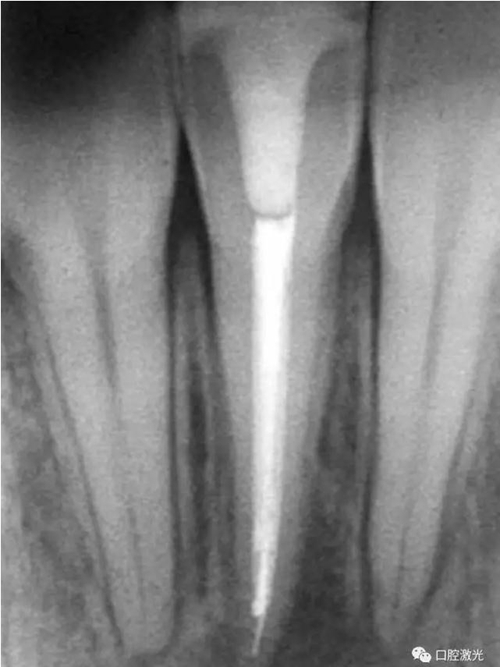

41 治療前X光片

激光治療中

6個(gè)月后治療效果